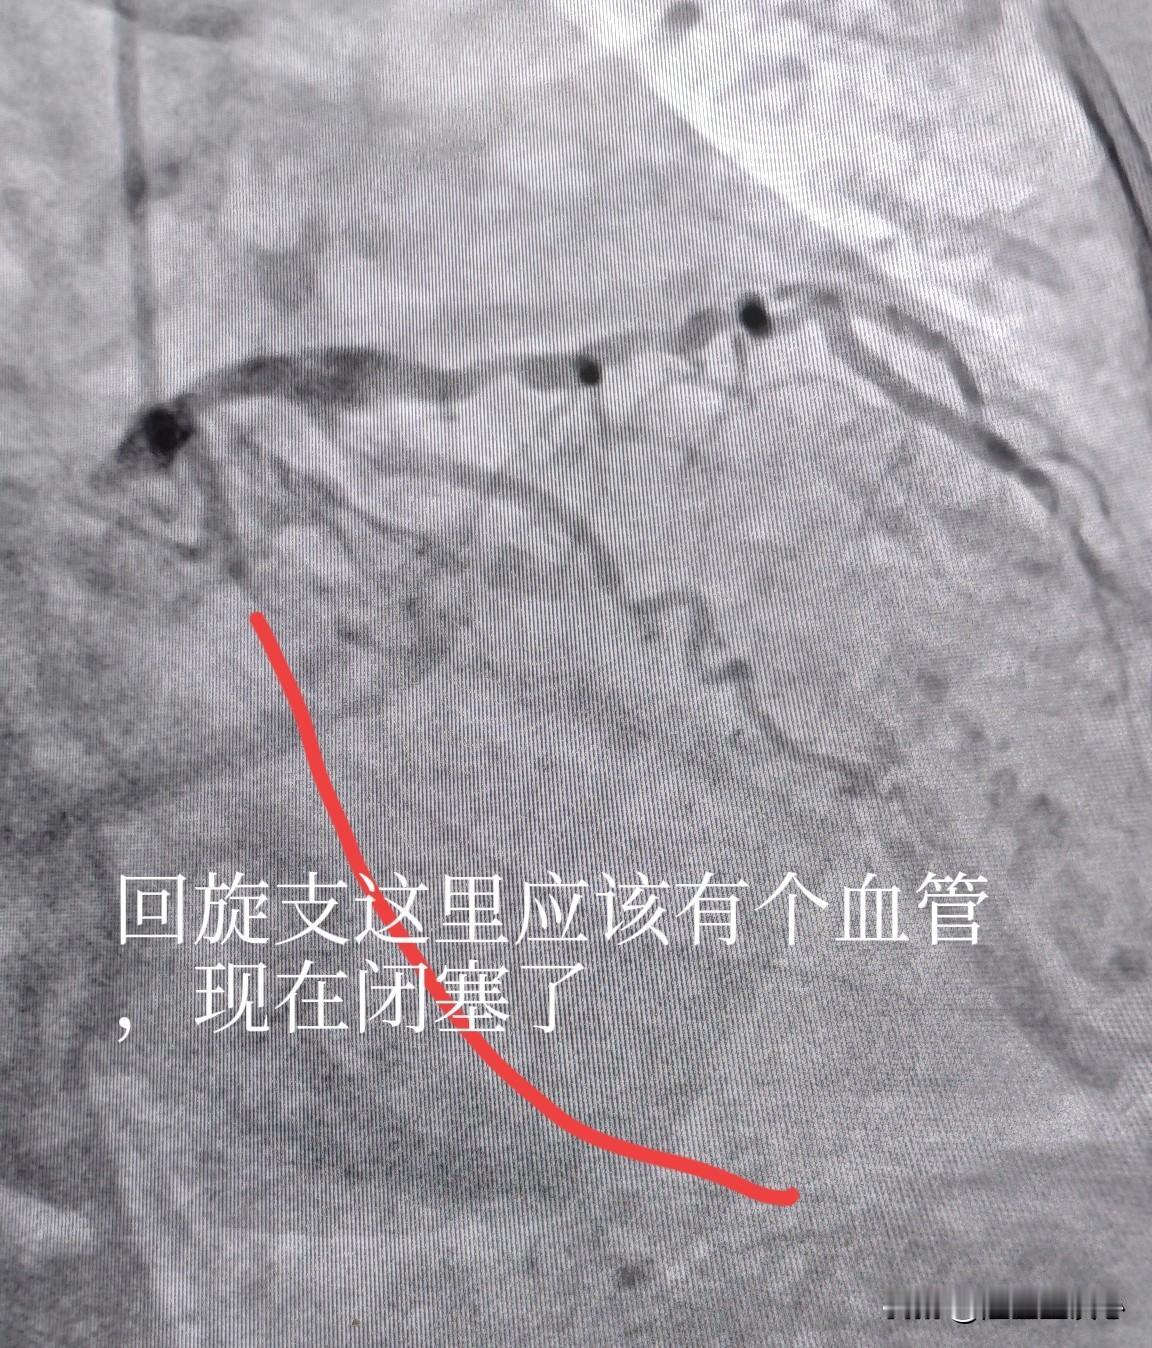

高龄女性,多根血管狭窄,耐受性差,低体重,分次手术更安全。75 岁女性患者,三支病变,前降支长节段重度狭窄,回旋支闭塞,右冠重度狭窄。 回旋支细小,供血范围相对比较小,有侧支循环,战略性放弃,就不开通了。主要精力放在右冠和前降支上面。 考虑到患者高龄,耐受性差,造影剂量大以后会影响到肾脏,引起肾功能恶化。今天先右冠做了2 枚支架。让患者休息一段时间后,身体休养一下。过段时间再来做前降支。